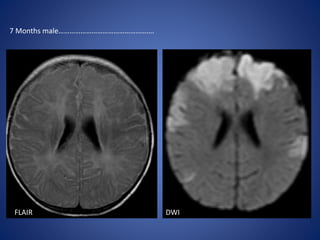

FLAIR DWI

7 Months male…………………………………………….